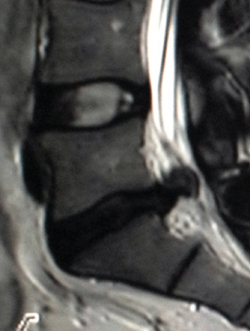

Resonancia magnética(19,21,24)

La RM constituye la técnica de imagen más moderna, con la ventaja de no utilizar radiaciones ionizantes, pero con el inconveniente de su precio, lo que limita su presencia en la totalidad de los centros sanitarios. Tiene también el inconveniente de no poder realizarse a pacientes tan obesos o voluminosos que necesiten una RM de mayor diámetro, así como provocar reacciones frecuentes de claustrofobia que obligan a realizar resonancias “abiertas”, de menor calidad de imagen.

Ofrece una excelente definición de las estructuras blandas (tanto intra- como extrarraquídeas). Permite una buena visualización del saco dural y su contenido, sin la necesidad de tener que inyectar contraste intratecal, además de permitir la detección de patologías intramedulares. Es, por tanto, la técnica diagnóstica de elección ante la sospecha de una patología específica de partes blandas, discos intervertebrales, ligamentos y saco neural, así como en la evaluación de una posible afectación tumoral, infecciosa o metabólica del raquis vertebral lumbar (Figura 13).

Figura 13. Hernia de disco extruida.

Las principales indicaciones para el empleo de esta técnica en el estudio de la patología dolorosa lumbar serían:

- La sospecha clínica de hernia discal: de elección, especialmente en pacientes jóvenes sin signos de espondilosis ni estenosis del canal vertebral; debería reservarse para pacientes candidatos a un tratamiento quirúrgico o aquellos que, con síntomas o signos de radiculopatía, no responden adecuadamente al tratamiento conservador pautado durante un periodo variable de 4 a 6 semanas.

- La estenosis del canal vertebral lumbar.

- La infección vertebral.

- Los tumores vertebrales.

- El traumatismo vertebral y su seguimiento, al detectar el edema residual de los cuerpos vertebrales fracturados en evolución.

- La lesión medular.

- Las malformaciones congénitas espinales

- La valoración del dolor lumbar tras una cirugía vertebral discal: constituye el único método diagnóstico para diferenciar una cicatriz fibrosa por una probable fibrosis posquirúrgica de una recidiva herniaria, con una precisión cercana al 98%.